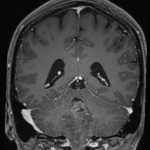

624

'25年4月

70代

後頭葉膠芽腫

頭蓋内腫瘍摘出術

No.’25_26 手術前1

No.’25_26 手術前2

No.’25_26 摘出 前

No.’25_26  摘出 中

No.’25_26 摘出 後